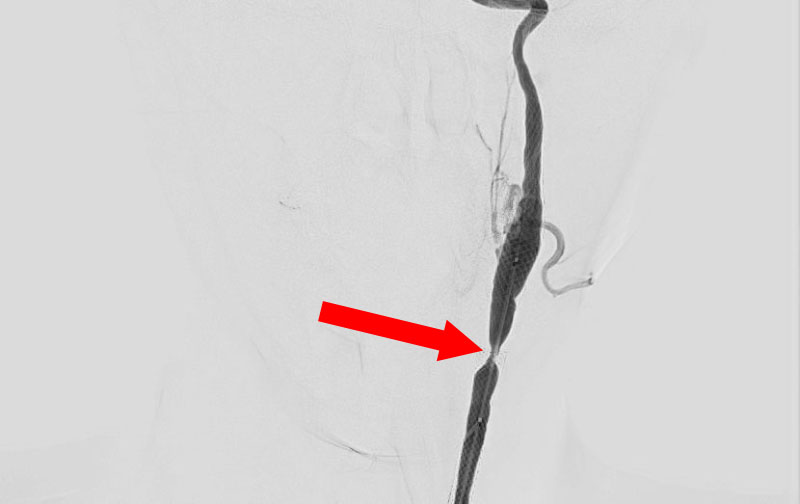

'25年10月

左総頚動脈狭窄症

30代

院内外来

No.1590 手術前

No.1590 手術後